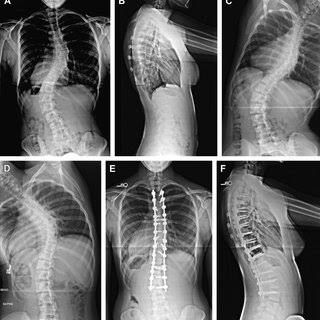

Escoliose

Deformidade da coluna que pode ocorrer por tendências genéticas, síndromes, doenças neurológicas ou desgaste intenso da coluna. Quando diagnosticada precocemente, deve ser acompanhada pois em alguns casos o uso de colete pode ser prescrito. Em casos onde há progressão da deformidade, compressão de nervos, dor intratável, pode-se instituir cirurgias corretivas para a deformidade.